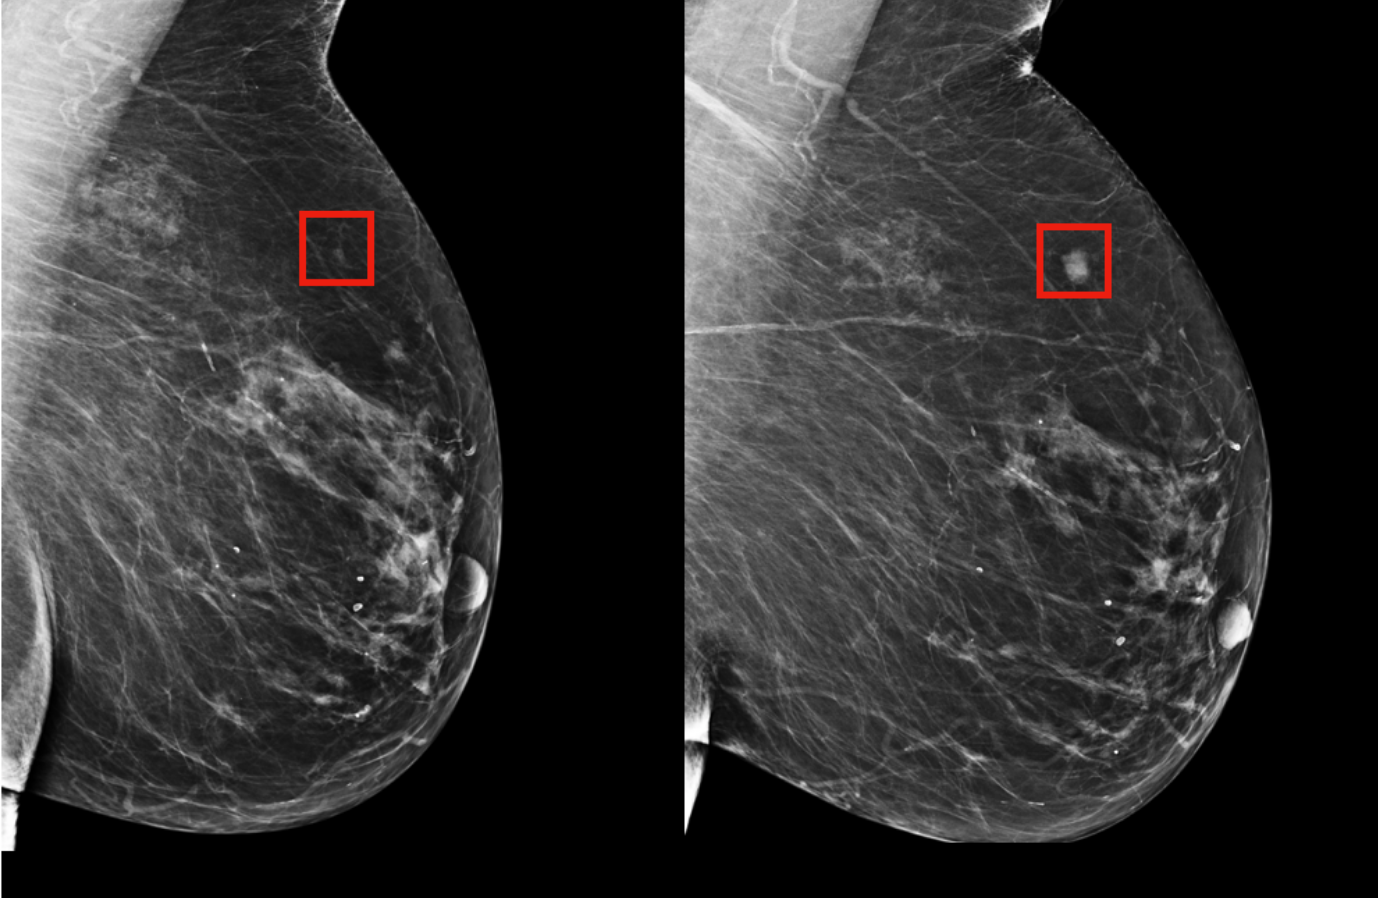

Para Norton, “la tecnología se va poniendo cada vez mejor”. La herramienta de IA que utilizó el Instituto de Tecnología de Massachusetts (MIT), predijo el cáncer de mama al identificar un área de “alto riesgo” en el seno de una mujer que desarrolló esta enfermedad cuatro años después.